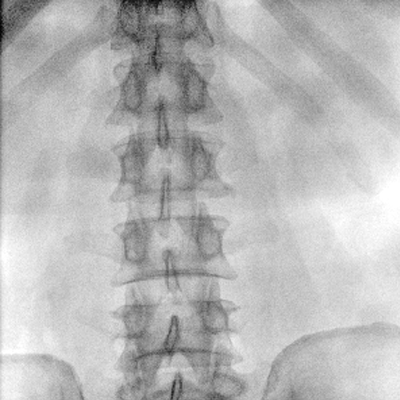

大尺寸動(dòng)態(tài)平板探測(cè)器,高DQE、低噪聲、圖像清晰。采用多分辨率圖像增強(qiáng)處理技術(shù),不同部位不同圖像處理算法,滿足客戶多樣化的需求。

采用智能變頻脈沖透視技術(shù),優(yōu)化圖像質(zhì)量的同時(shí)降低輻射劑量,呵護(hù)醫(yī)患健康